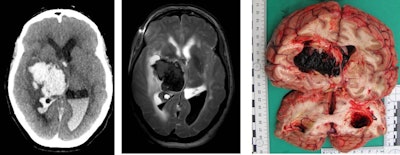

Brain hemorrhage due to hypertension or vessel anomalies is a natural death -- this finding in the postmortem imaging can allow such cases to be closed without open invasive autopsy. Images courtesy of Dr. Michael Thali.

Brain hemorrhage due to hypertension or vessel anomalies is a natural death -- this finding in the postmortem imaging can allow such cases to be closed without open invasive autopsy. Images courtesy of Dr. Michael Thali.CT triage